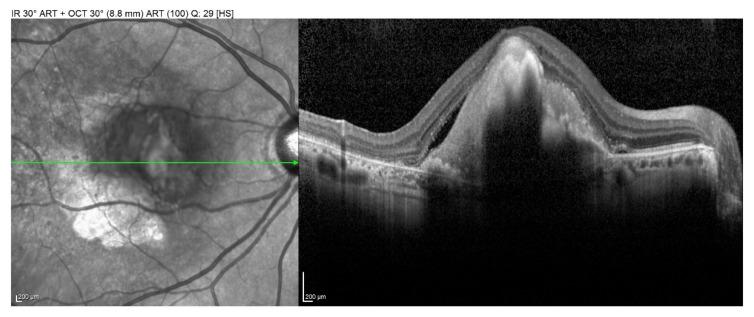

Oral pathogens have been identified in bioptic specimens from Age-Related Macular Degeneration (ARMD) patients, and alveolar bone loss has been related to ARMD. Therefore, the possible association between ARMD and periodontal disease was investigated in the present case-control study, evaluating clinical and radiographic periodontal parameters, primarily, in cases vs. controls and, secondarily, in relation to ARMD risk factors, in cases, to highlight a possible pathogenic link between the disorders. Forty ARMD cases and 40 non-ARMD controls, matched for age (±3 years) and gender and homogeneous for ARMD risk factors, therefore comparable, underwent full-mouth periodontal charting, panoramic radiograph, and medical data, including ARMD risk factors, collection. Statistical analysis was conducted using the language R. Comparisons between groups were made using both traditional -tests and Yuen's test with bootstrap calibration. Enrolled subjects were ≥55 years old, and 50 females and 30 males were equally distributed among the two groups. No statistically significant difference was found in clinical and radiographic periodontal parameters in cases vs. controls. In the case group, no differences were found when relating the periodontal parameters to ARMD risk factors, except for Clinical Attachment Level values that were statistically significantly higher in hypertensive ARMD subjects. A possible association between periodontal disease and ARMD may be hypothesized in hypertensive ARMD subjects, with hypertension as a possible pathogenic link between the disorders.

在年龄相关性黄斑变性(ARMD)患者的活检标本中已鉴定出口腔病原体,并且牙槽骨丧失与ARMD有关。因此,在本病例对照研究中调查了ARMD与牙周病之间可能存在的关联,主要评估病例组与对照组的临床和影像学牙周参数,其次评估病例组中与ARMD危险因素相关的参数,以突出这两种疾病之间可能的致病联系。40例ARMD病例和40例非ARMD对照,年龄匹配(±3岁)、性别相同且ARMD危险因素相同,因此具有可比性,接受了全口牙周检查、全景X线片检查,并收集了包括ARMD危险因素在内的医学数据。使用R语言进行统计分析。组间比较采用传统的t检验和带自助校准的Yuen检验。纳入的受试者年龄≥55岁,两组中女性50名、男性30名分布均匀。病例组与对照组在临床和影像学牙周参数方面未发现统计学上的显著差异。在病例组中,将牙周参数与ARMD危险因素相关联时未发现差异,但高血压性ARMD受试者的临床附着水平值在统计学上显著更高。在高血压性ARMD受试者中可以假设牙周病与ARMD之间可能存在关联,高血压可能是这两种疾病之间的致病联系。